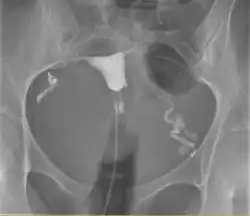

![]() A normal hysterosalpingogram. Note the catheter entering at the bottom of the screen, and the contrast medium filling the uterine cavity (small triangle in the center). | |

Hysterosalpingography (HSG), also known as uterosalpingography,[1] is a radiologic procedure to investigate the shape of the uterine cavity and the shape and patency of the fallopian tubes. It is a special x-ray procedure using dye to look at the womb (uterus) and fallopian tubes.[2] In this procedure, a radio-opaque material is injected into the cervical canal, and radiographs are taken. A normal result shows the filling of the uterine cavity and the bilateral filling of the fallopian tube with the injection material. To demonstrate tubal patency, spillage of the material into the peritoneal cavity needs to be observed. Hysterosalpingography has vital role in treatment of infertility, especially in the case of fallopian tube blockage.